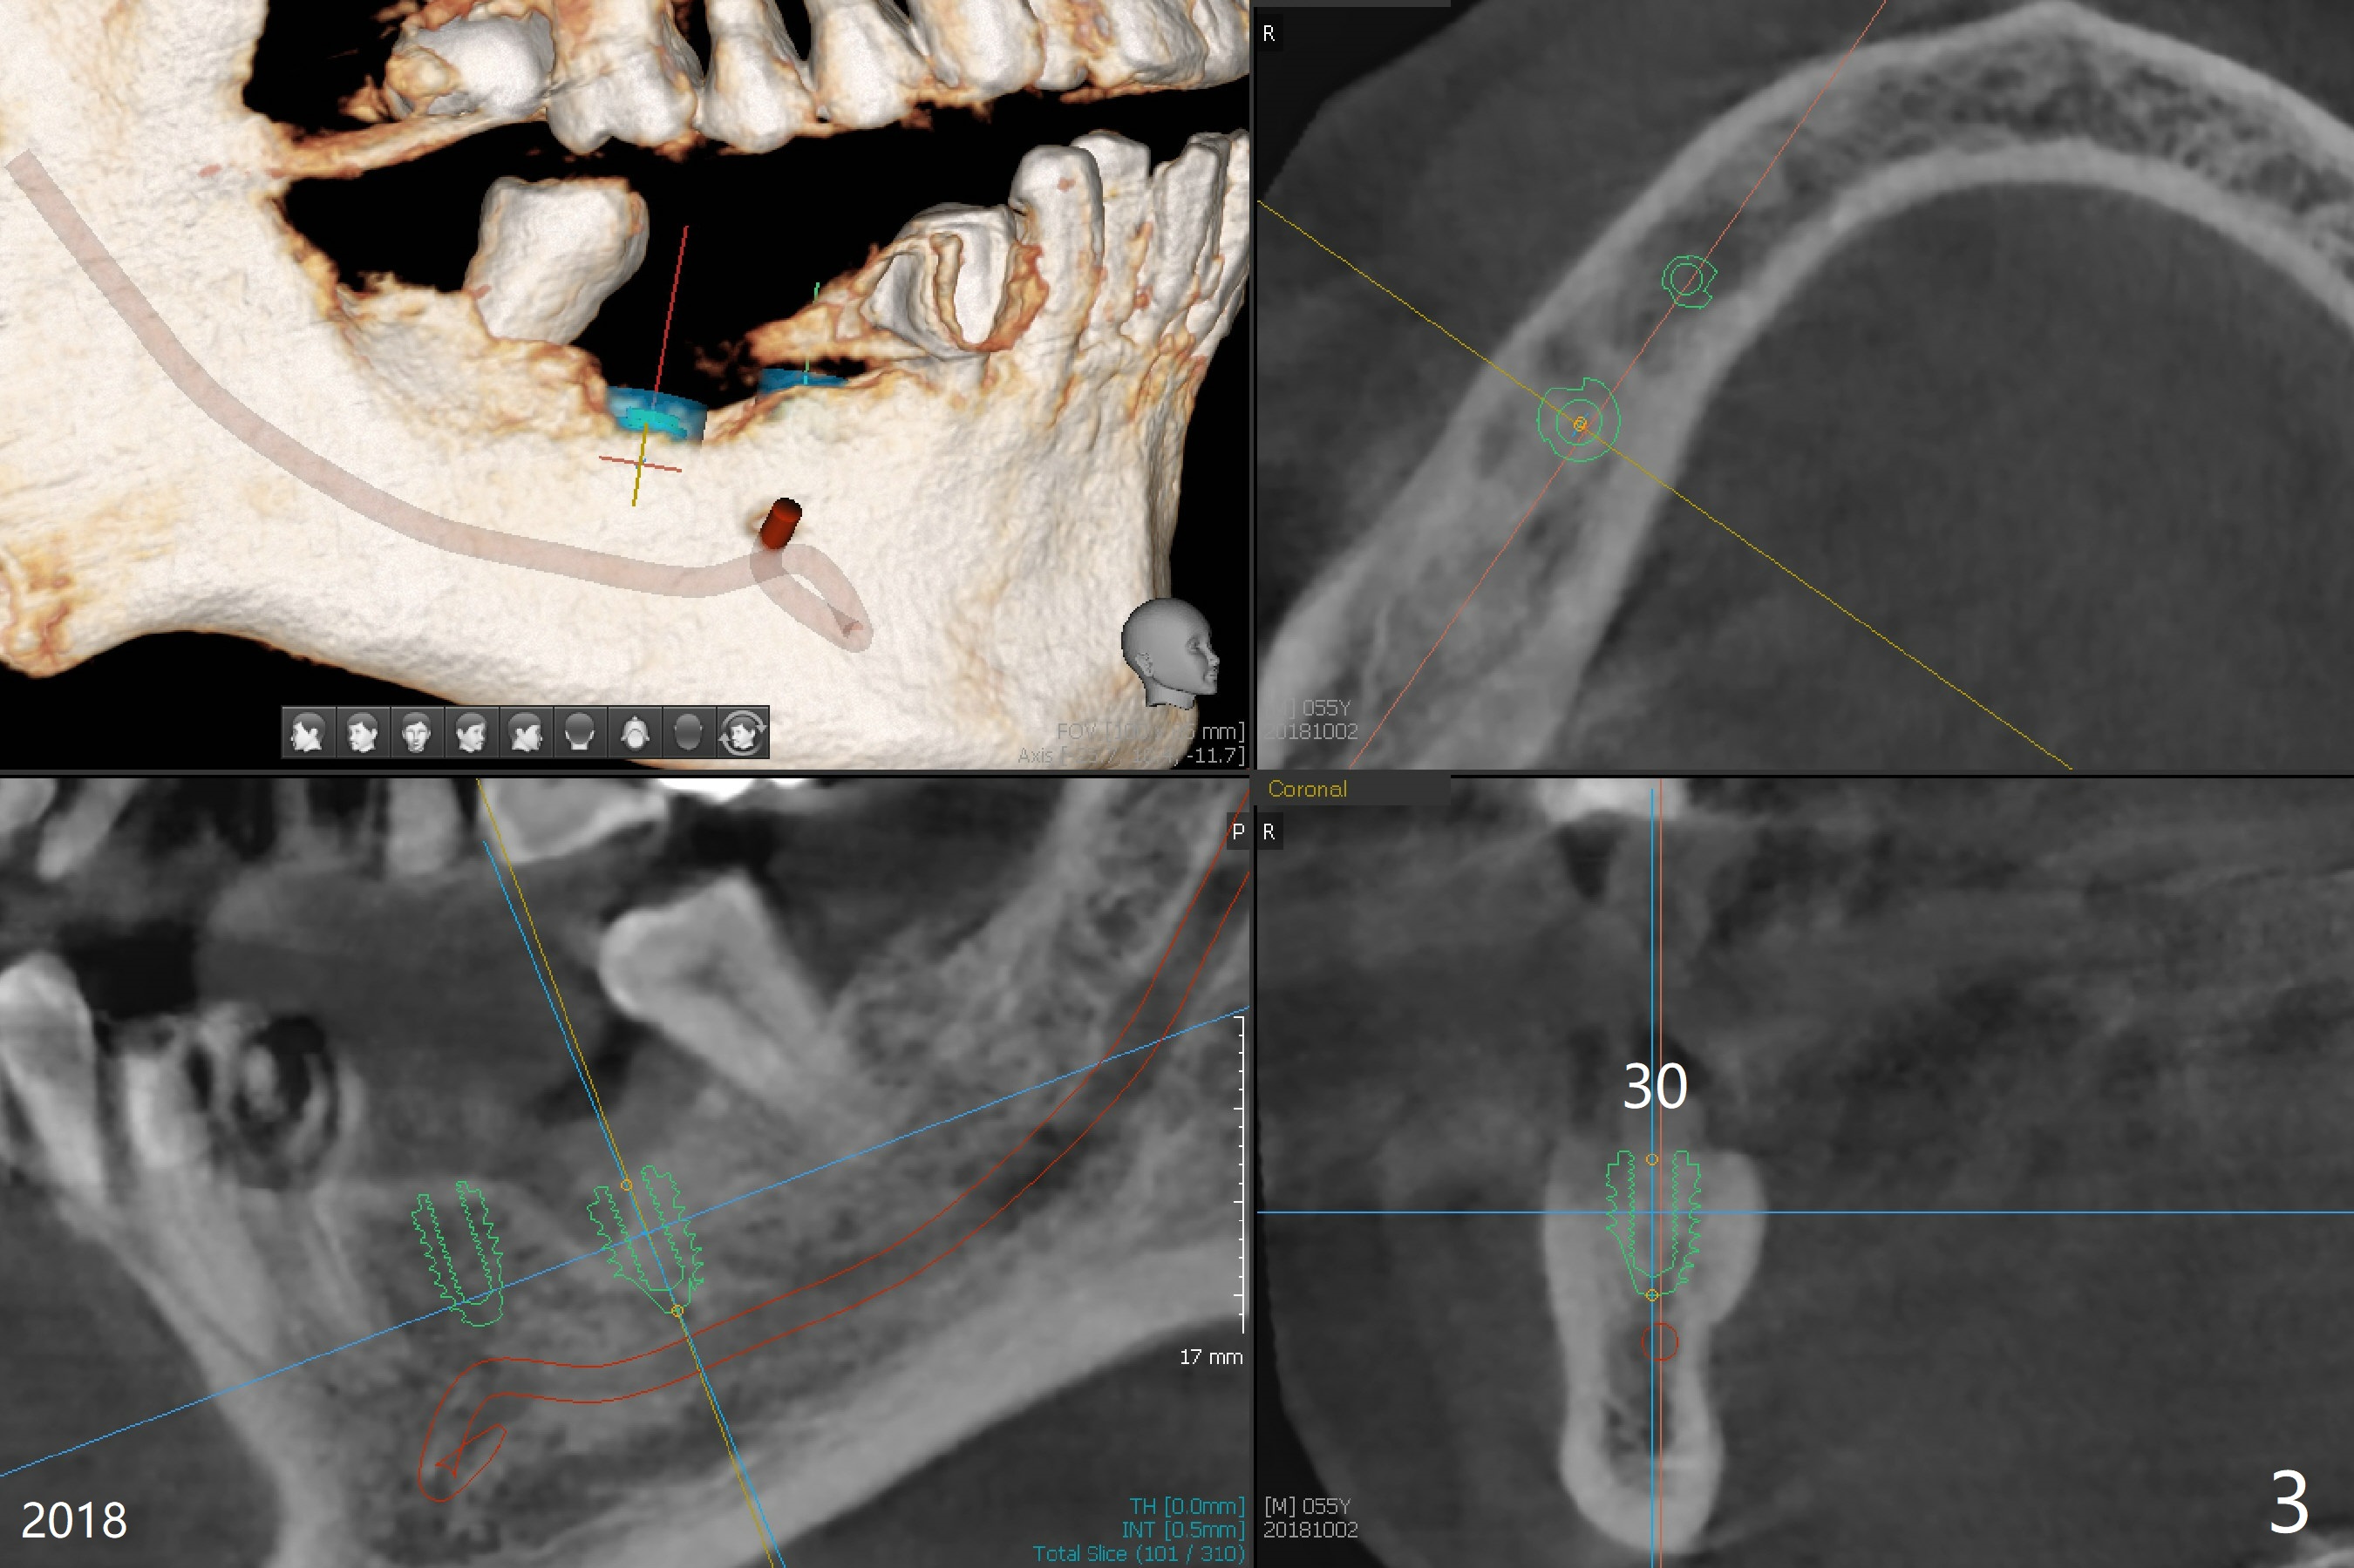

A 55-year-old man had #30 extracted and #29 pontic removed ~ 3 months ago (Fig.1,2). Short implants are to be placed (4.5x8.5 and 5x7.3 mm) with guide. Pay attention to the submandibular fossa (Fig.2 *) as related to the site of #30. New CT (Fig.3,4 (2018)) shows that implants will be 4x7.3 and 5x7.3 mm.